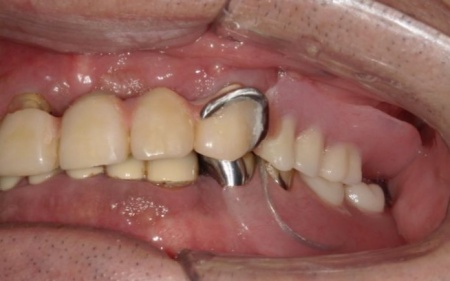

噛む機能の回復と自然な見た目の両方を実現するため、インプラントオーバーデンチャーによる治療を提案しました。

インプラントオーバーデンチャーとは、顎の骨に埋め込んだインプラント(人工歯根)を支えとして、取り外し可能な義歯を装着する治療法です。

従来の義歯と比べてしっかりと固定できるためずれにくく、噛む力の向上が期待できる一方で、外科処置が必要である点、治療期間がやや長期になる点がデメリットといえます。

まずは、歯根を支える骨が溶けてなくなる歯周病が進行しており、長期的な維持が難しいと判断した左下奥歯(第2小臼歯)を丁寧に抜きます。

次に、上下左右の奥歯部に1本ずつ、左上前歯に1本、計5本のインプラントを埋入する手術を行いました。

続いて、残存している上の歯に対しては根管治療を行いました。

根管内の感染源を慎重に除去したうえで、再感染を防いで歯を長く使用するために、薬剤でしっかりと密閉しています。

ただ、右上前歯(犬歯)は状態が十分に改善せず、温存が困難であると判断したため、抜歯を行いました。

根管治療が終了した上の歯には、オーバーデンチャーの支えとなる内冠(入れ歯を安定させるための土台)を、インプラント部分にはロケーター(義歯をしっかり固定するための連結装置)を装着しました。

この仕組みにより、必要に応じて入れ歯の取り外しを可能にしながら、日常生活では安定した状態を保つことができます。

次に上下顎に装着するため、チタン床を使用した金属床義歯を作製しました。

チタンは軽量でありながら強度が高く、体になじみやすい特徴をもつ素材です。また、金属床にすることで従来の樹脂製義歯と比べて薄く作ることが可能になり、装着による違和感の軽減も見込めます。

また、上顎は残存歯が少ないためすべてを覆う総入れ歯で、下顎は前歯がしっかり残っているため部分入れ歯の形で作製しました。

完成した入れ歯を装着していただき、噛み合わせや義歯の安定性、見た目の仕上がりに問題がないことを確認して、治療を終了しています。